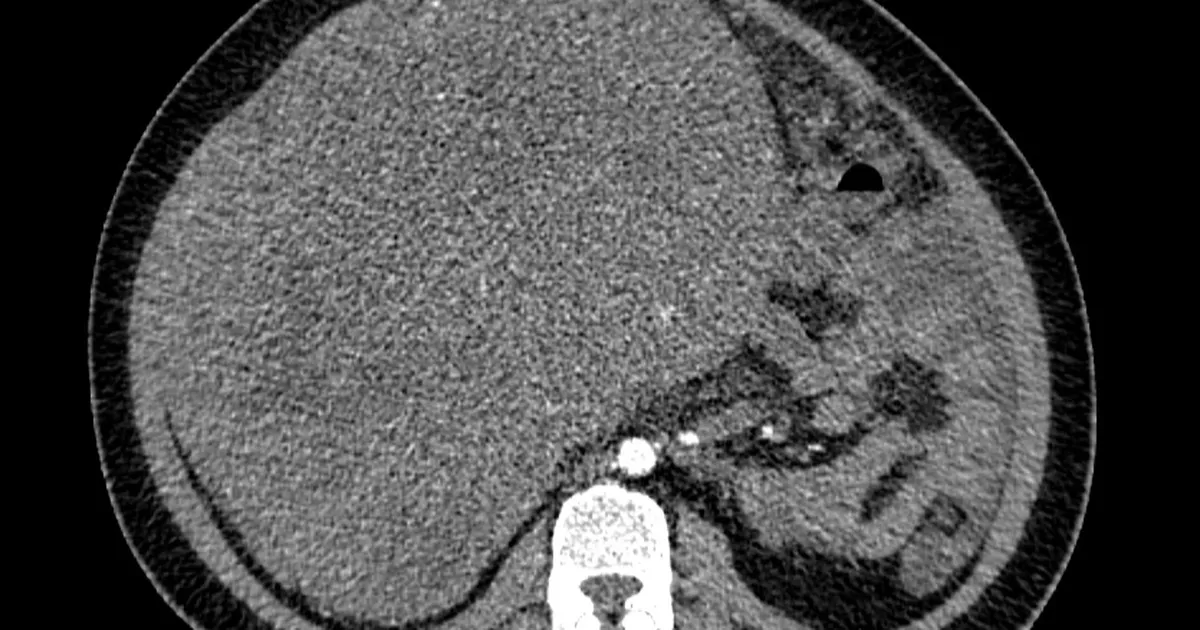

Khi khối u đáp ứng điều trị, các bác sĩ tiến hành phẫu thuật cắt bỏ khối u nguyên phát tại đại tràng. Tuy nhiên, thách thức lớn hơn nằm ở gan, nơi tế bào ung thư đã di căn.

David tiếp tục được xạ trị chuyên biệt, đồng thời được đưa vào danh sách chờ ghép gan. Cơ hội đến khi có nguồn gan hiến phù hợp. Ca ghép được thực hiện thành công, anh nằm viện hai tuần trước khi hồi phục dần.